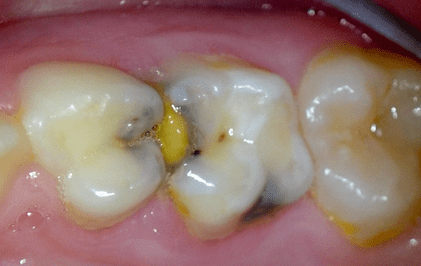

Frühkindliche Karies ist auf dem Vormarsch. Einfache, praxisbewährte Konzepte zur Betreuung von Kleinkindern können das Problem frühzeitig...

Frühkindliche Karies ist auf dem Vormarsch. Einfache, praxisbewährte Konzepte zur Betreuung...